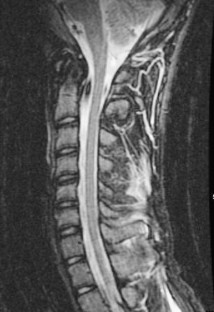

Fig. 2